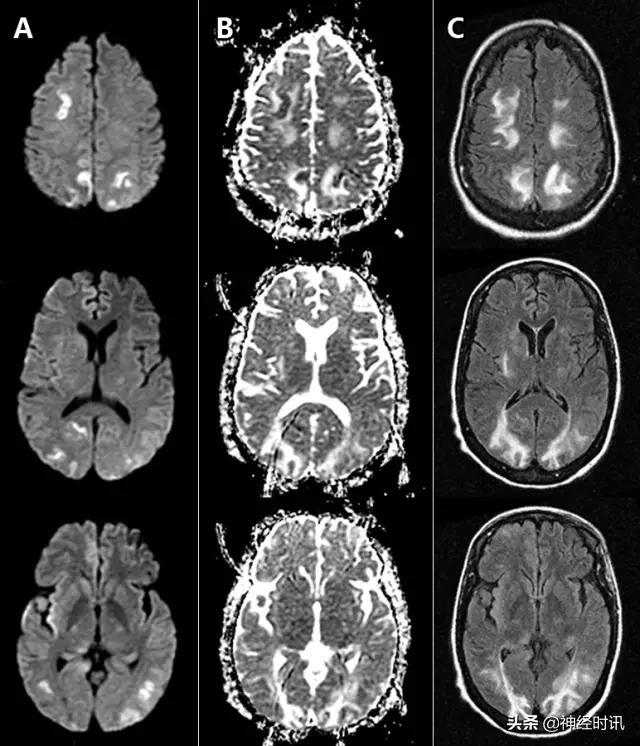

图7 一例31岁男性,有*洛因海**和*卡因可**滥用史,出现无脉性电活动心搏骤停。MRI显示双侧顶枕叶和额叶、双侧丘脑弥漫性弥散受限(A:DWI,B:ADC)、T2-FLAIR高信号(C:FLAIR),符合全脑缺氧性损伤。

图8 一例62岁女性,复视3个月,听力丧失数天,因眩晕、恶心、呕吐、眼震和厌食来诊。她被诊断为营养缺乏导致的Wernicke病,硫胺素水平为35 nmol/L (正常70–180)。MRI显示四叠体板、中脑导水管周围灰质、下丘脑和双侧上丘FLAIR高信号和各种不同程度的弥散(A:DWI,B:ADC)。

图9 一例53岁女性,酒精性肝硬化,因腹痛、恶心和呕血就诊于急诊。数天后,她出现无反应,伴脑干反射消失,血*水氨**平达360。她被诊断为肝性脑病,MRI显示双侧额叶和岛叶皮层和丘脑轻度弥散受限(A:DWI,B:ADC)和FLAIR高信号(C)。豆状核有轻度T1高信号(D)。